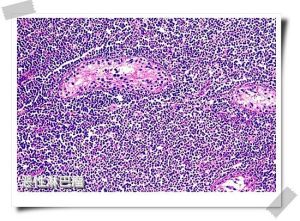

顯微鏡下所見:睪丸淋巴瘤,幾乎都是非霍奇金淋巴瘤,霍奇金淋巴瘤極為罕見。除了個別病人組織學結構為結節性淋巴瘤外,所有的睪丸淋巴瘤均為瀰漫性。然而,由於早年的病例未採用統一的分類標準,採用的術語亦不盡相同,分類中的大多數是網織細胞肉瘤,其次是淋巴細胞型淋巴瘤。後來大部分臨床報告均採用Rappaport分類,在一組用該方法分類的170例病人中,瀰漫性組織細胞型占76%,低分化淋巴細胞型占14%,瀰漫性混合細胞型占3%,其他類型占7%。Rappaport分類中瀰漫性組織細胞型淋巴瘤,實際上是一組免疫學及形態學上很複雜的疾病,基本上這種亞型被歸入預後差的淋巴瘤。Paladugu等報告了20例瀰漫性組織細胞型淋巴瘤,其中19例為大無裂細胞型,與大裂細胞淋巴瘤相比,大無裂型預後差且對化療不敏感。採用國際工作方案分類法,3個系列69例睪丸淋巴瘤,47例為中度惡性,21例為高度惡性,僅1例為低度惡性。

大體標本:睪丸腫瘤鶒的大體標本腫瘤主要侵犯睪丸體通常被完整的睪丸鞘膜覆蓋,精囊和附睪一般均受侵犯。大體標本切片觀察,腫瘤結構排列均勻睪丸被瀰漫侵犯,常呈結節狀,可以是多發性,亦可為單發。常伴有出血及壞死,通常為灰色、淺黃色、淺紅色及褐色。顯微鏡下所見:睪丸淋巴瘤,幾乎都是非霍奇金淋巴瘤,霍奇金淋巴瘤極為罕見。除了個別病人組織學結構為結節性淋巴瘤外,所有的睪丸淋巴瘤均為瀰漫性。然而鶒,由於早年的病例未採用統一的分類標準採用的術語亦不盡相同,分類中的大多數是網織細胞肉瘤,其次是淋巴細胞型淋巴瘤。後來大部分臨床報告均採用Rappaport分類,在一組用該方法分類的170例病人中,瀰漫性組織細胞型占76%;低分化淋巴細胞型占14%;瀰漫性混合細胞型占3%;其他類型占7%。Rappaport分類中瀰漫性組織細胞型淋巴瘤,實際上是一組免疫學及形態學上很複雜的疾病,基本上這種亞型被歸入預後差的淋巴瘤鶒Paladugu等報告了20例瀰漫性組織細胞型淋巴瘤,其中19例為大無裂細胞型與大裂細胞淋巴瘤相比大無裂型預後差且對化療不敏感鶒。採用國際工作方案分類法,3個系列69例睪丸淋巴瘤,47例為中度惡性21例為高度惡性,僅1例為低度惡性 ;